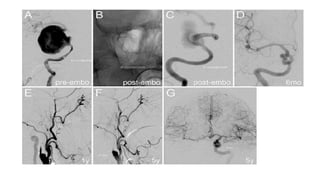

Endovascular Treatment of Aneurysms

v

• In those patients in whom giant aneurysms can be surgically

clipped with acceptable risks of morbidity and mortality, that

approach remains the treatment of choice because the

embolization option does not appear to offer the same durability of

protection from rupture.

Endovascular Treatment of Aneurysm cont..

Coiling

Parent

vessels

occlusion

Balloon

Remodelling

Technique

Stents and

Treatment

Endovascular Treatment ofAneurysms v • In those patients in whom giant aneurysms can be surgically clipped with acceptable risks of morbidity and mortality, that approach remains the treatment of choice because the embolization option does not appear to offer the same durability of protection from rupture.

Endovascular Treatment ofAneurysm cont.. Coiling Parent vessels occlusion Balloon Remodelling Technique Stents and Treatment